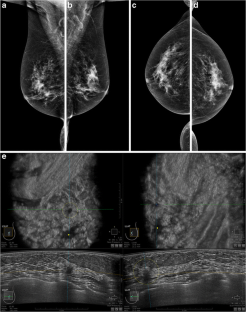

Fig. 2